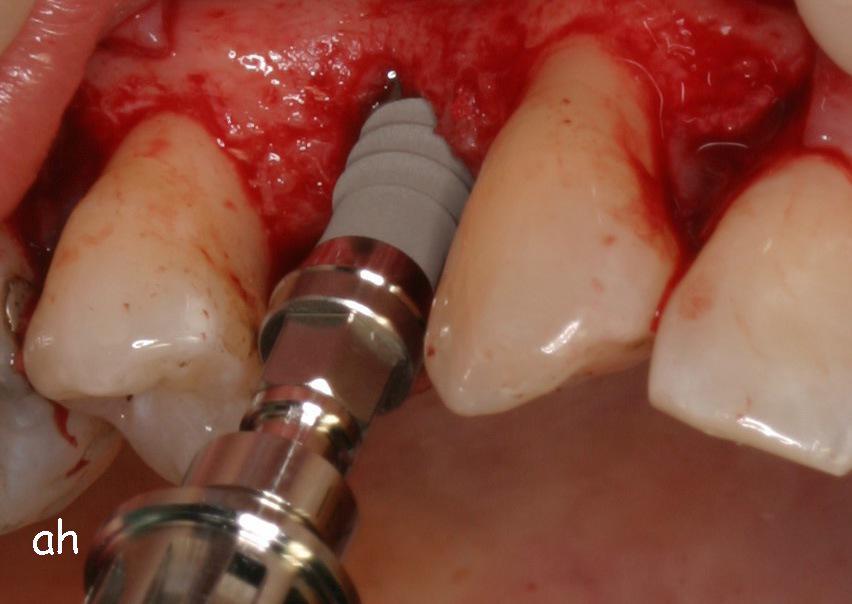

Exemple 1: Ce patient a perdu son incisive centrale gauche lors d'un accident. Un implant a été posé

Exemple 1: L'implant remplace la racine de la dent manquante